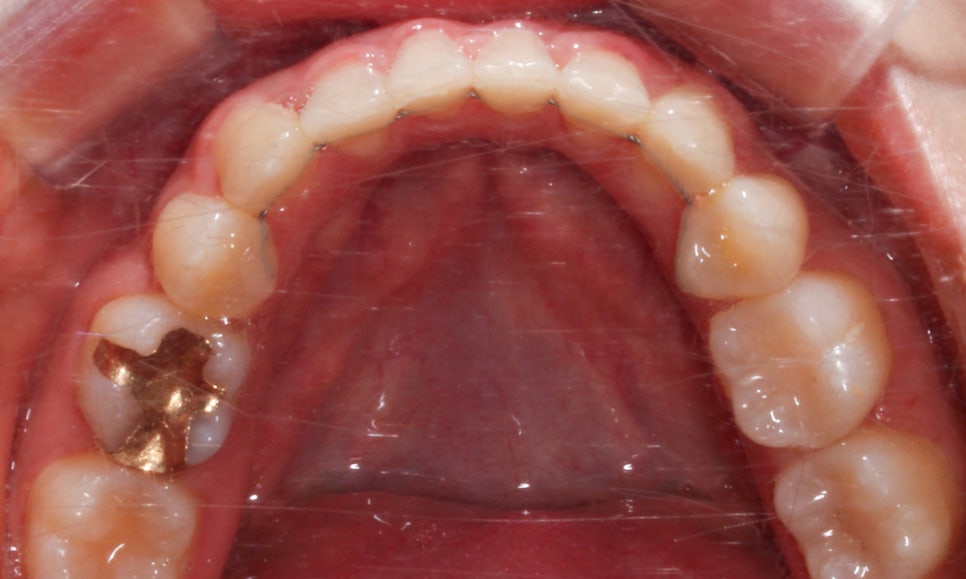

역삼역치과 덧니교정 Case의 하악 교합면 사진입니다.

양쪽 측절치의 각도를 보시면 설측으로

밀려 들어와 있는 느낌이 강한데요,

이러한 경우 악궁의 길이와 치아의 크기가

조화롭지 못하여 발생하는 문제일 가능성이

크기 때문에 모든 치아에 ligature wire를

결찰하기 전 open coil spring으로

치아 사이의 공간을 충분히 넓혀준 뒤

치아 배열을 바로잡는 것이 좋습니다.